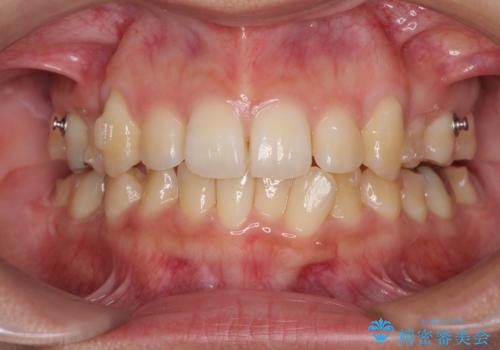

八重歯の抜歯矯正 補助装置を用いたインビザライン矯正

- 下の前歯のデコボコを気にして来院された患者様です。

来院当初、上顎の八重歯は気にしていらっしゃらなかったのですが、矯正治療をするのであれば、しっかりと治した方が良いと説明し、全顎矯正を行うこととしました。

八重歯の移動量が多く、インビザライン単体での治療は困難と判断し、補助装置により八重歯移動後にインビザラインを用いることとしました。